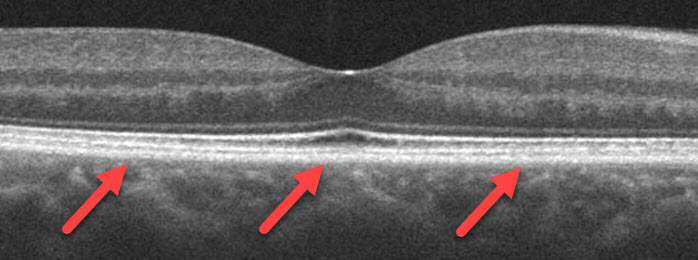

The normal eye is a round ball about 24 mm (0.94 inches) in diameter. Far-sightedness (hyperopia) occurs when the eye is shorter than normal and near-sightedness (myopia) when the eye is larger. In degenerative myopia the eye becomes elongated, and the retinal and orange choroidal tissues that line the eye become thinned. There can also be frank out-pouchings (posterior staphyloma) of the macula.

Some patients can develop splitting of the retinal tissue (macular retinoschisis) due to macular pucker, vitreomacular traction, or to the macular tissue being stretched by the elongation of the eye. This can cause central vision loss and distortion.